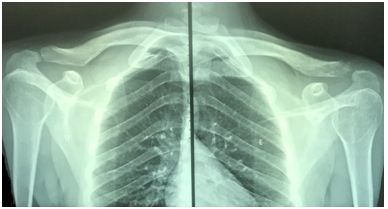

The average time before returning to usual activities was 20.7 weeks, the shortest being 16 weeks, and the longest, 30 weeks. The radiological control for contralateral comparison regarding the coracoclavicular distance showed similar or lower level in 14 patients, elevation lower than 50% in three, between 50 and 100% in two, and higher than 100% in one patient.

The UCLA score was applied at 6, 12, and 25 weeks. The average number of points after six weeks was 21.7; after 12 weeks, 29.95; and after 25 weeks, 33.95, with variation between 30 and 35. After 25 weeks (when the UCLA score was last applied in the follow-up), 14 patients had 35 points, classified as an excellent result according to the Ellman criteria, and six had between 30 and 33 points, classified as good (Figure 3).

Figure 3 Post operative radiograph. Left: normal shoulder. Right: operated shoulder.